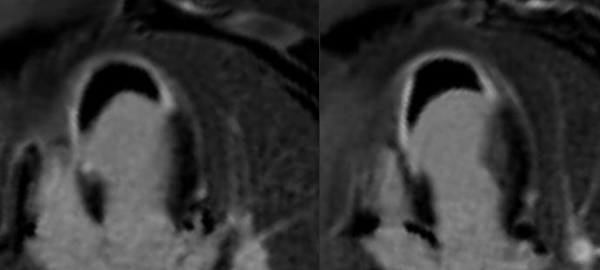

Evaluation of Cardiac mass

Cardiac MRI does not show vegetations, easily especially if small. However, evaluating the transaxials through the valve may help pick up small nodules and to rule out mimics.